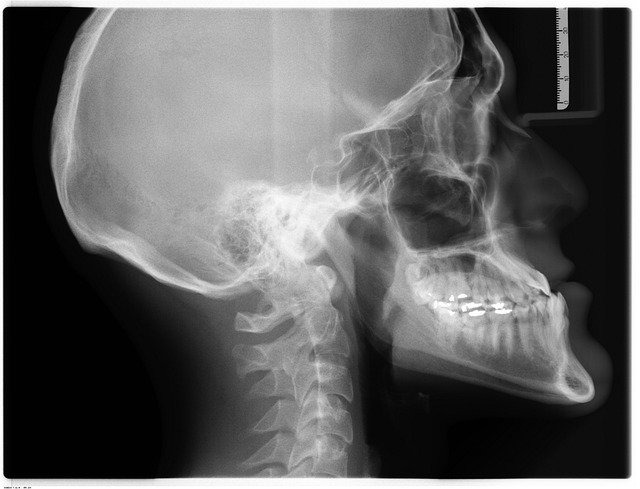

しかし、このような自覚症状があってもレントゲンやCT、MRIなどの画像検査では、怪我の原因を判断することができない場合があります。怪我や症状の原因の特定が難しい場合があるということを、まずは覚えておきましょう。

むちうち患者のレントゲンを見る医師

AlarconAudiovisual

むちうち患者のレントゲン

digitalartstudiospr

整形外科で画像検査を受ける場合は、レントゲンやCTだけでなく、MRI検査も受けるようにしてください。

レントゲンは、骨の異常を発見することに向いているため、骨折や骨にできたヒビを見つけることはできますが、神経や靭帯、筋肉といった軟部組織の異常を見つけることはできません。

しかしMRI検査では、軟部組織を写せる可能性があるため、筋肉や靭帯などの異常を発見でき、むちうちであると証明できる可能性があります。

もしも、MRI検査で原因が判別できない場合でも、神経学的検査を受けることができます。

神経学的検査とは、医師が手や器具などで患部を直接刺激し、異常を見つけるための検査です。神経学的検査には、ジャクソンテストやスパーリングテスト、神経根症状誘発テスト、筋萎縮検査などさまざまな種類があり、むちうちの症状を明らかにできる場合があります。